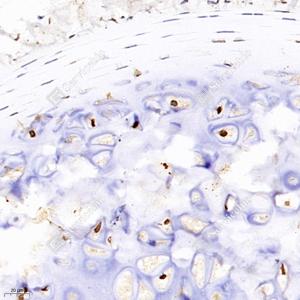

IHC检测GDF6蛋白(货号 GB111654). 样品: 大鼠软骨, 4%多聚甲醛 (货号G1101) 固定12-24小时. 抗原修复: 柠檬酸抗原修复液(干粉, pH 6.0) (G1201), 98℃, 20分钟. —抗: 1: 700稀释, 4℃ 孵育过夜. 二抗: HRP标记山羊抗兔IgG (H+L) (货号GB23303), 1: 200稀释, 室温孵育1小时. |